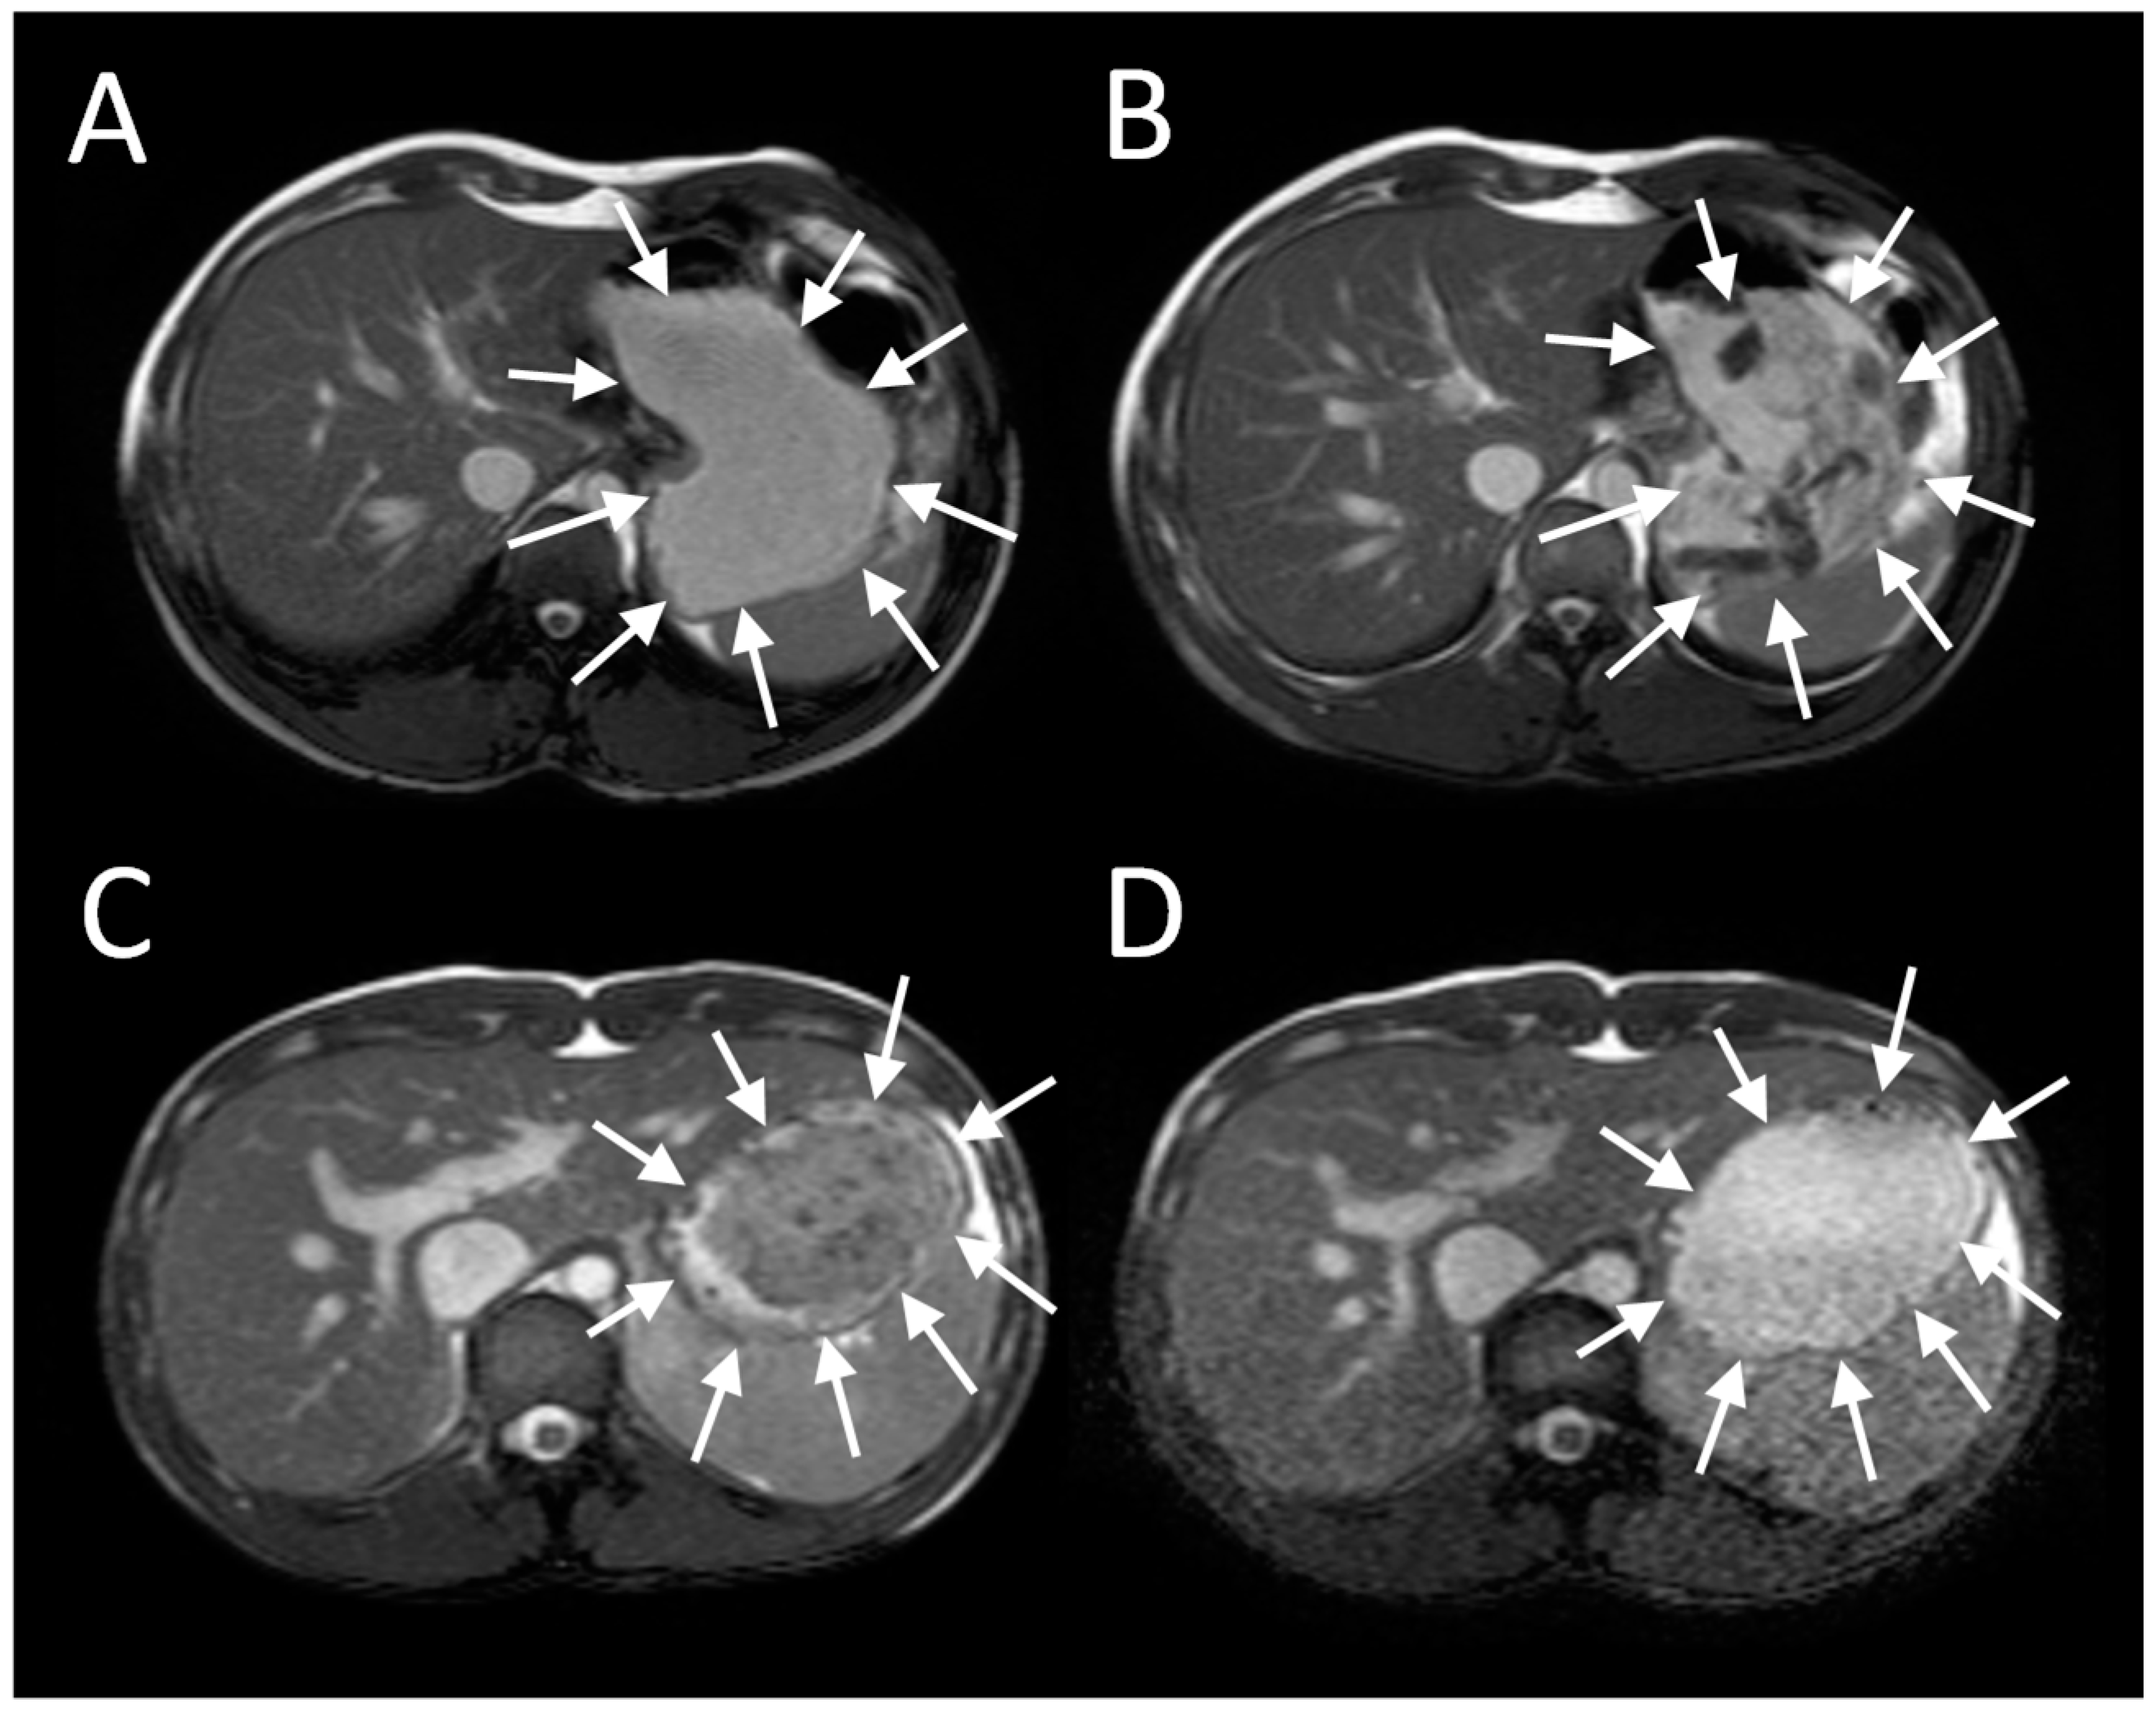

Imaging of intra-gastric contents demonstrates a wealth of detail previously unrecognized and unmeasurable when studies were limited to measurement of merely the rate of gastric emptying using scintigraphy (Figure 1). When food is ingested, chewing and mixing with saliva play a crucial role in modifying its consistency to form a bolus, whose physical properties allows easy passage past the larynx and down the oesophagus into the stomach [1]. The successive food boluses are accommodated within the stomach by reflex fundal relaxation. Soon after ingestion, antral contractions, starting mid-way down the lesser curvature, elute material from the outside of the solid component of the meal into the antrum and thence through the pylorus. MRI sequences sensitive to flow have been used to demonstrate the backward and forward movements induced by a combination of antral contractions and pyloric closure, which results in both retropulsion of contents back into the antrum and propulsion of a fine stream through the pylorus [2]. The retropulsive movements we observed were most marked after mixed nutrient fat/protein/carbohydrate meals compared to 5% or 10% glucose. The shear forces generated by antral grinding are surprisingly small compared to those in the mouth, and when assessed from the force required to break agar gel beads were found to be <0.65 newton [3].

The antral contractions are typically propulsive as they commence in the mid stomach but as they approach the pylorus change to a more systolic pattern with pyloric closure occurring before all the chyme is expelled into the duodenum. This effectively restricts gastric emptying to particles <2 mm in diameter and creates shearing forces as the remaining material is forced backwards away from the contracting pylorus. The resulting forward and backward flows can be detected using flow sensitive MRI sequences as mentioned previously. The net effect is the earlier emptying of the fluid component of mixed liquid/solid meals, which make up most of what normal humans ingest. MRI images can clearly show the heterogeneity of food immediately after food ingestion, which varies according to the meal type (Figure 1). A rice pudding meal typically separates into an uppermost fluid layer above a dependent solid component, whereas a roast chicken and vegetable meal produces a very heterogeneous intragastric distribution of solid and liquid. Other more homogenous meals like porridge, soup or bread produce a uniform intra-gastric mass from which no separation of the liquid and solid phase is possible. When we compared an equicaloric rice meal with wholemeal bread, we found that while the rice pudding meal separated into a solid and liquid phase, the wholemeal bread formed a rather homogeneous mass with no clear separation of fluid and solid. While the rice meal allowed the stomach to sieve the meal and empty the fluid faster than the solid, sieving was not possible with the more homogeneous bread meal and as a consequence the gastric volume fell more slowly. In contrast, once the wheat entered the small intestine it was rapidly absorbed and the small bowel water content (SBWC) was consistently lower than after the rice meal postprandially, suggesting than any sensation of bloating after a bread meal most probably comes from gastric distension [4]. Other groups have also used MRI to document gastric sieving and its prevention by homogenization with both solid [6] and liquid [7] meals.

Figure 1. Gastric MRI images of different mixed solid/liquid meals: (A) Soup, (B) roasted chicken and vegetables, (C) whole wheat bread and (D) rice pudding. Reproduced from [4], Springer Nature 2013, under Creative Commons CC-BY license and from [5], Oxford University Press 2012, with permission.

Nutrients 11 01147 g001